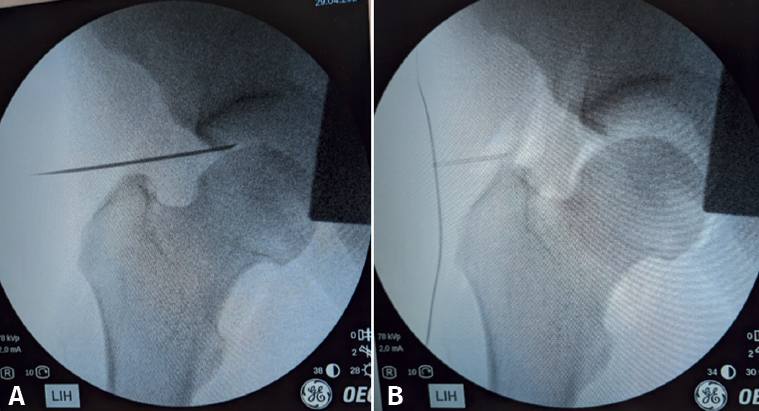

Another technique we can use to facilitate distraction is disruption of the joint seal by insufflating air (30 ml) into the joint with an 18 gauge needle under radiological control, after initial traction. This will create a positive pressure within the joint capsule, eliminating the native negative pressure, and thus facilitating further distraction of the joint. The insufflation of air into the joint will allow us to check that we are inside the joint by delimiting a radiolucent area corresponding to the joint capsule (Table 3).

We perform the AL arthroscopic portal under fluoroscopic control to confirm positioning of the guide needle. The guide is inserted with the bevel facing towards the femoral head in order to avoid damaging the cartilage of the latter. We visualize the location of the coxofemoral joint seeking to triangulate the entry point so that we access from the most lateral part of the acetabulum. To do this, we can imagine a line halfway between the pubis and the ASIS. As a general rule, the guide needle is oriented about20° in the cephalic direction. If we have adequately corrected the patient's femoral anteversion with internal rotation of the leg, as explained above, we should be able to enter with a direction parallel to the ground. By palpation, we detect the initial resistance of the fascia lata and, secondly, the resistance of the joint capsule, identifying the entry in the joint. We check the intra-articular location through palpation with nitinol wire (with blunt ends), touching with the acetabular fundus and via radioscopy control. We insufflate 30 ml of air to help us identify the rim of the acetabular labrum and physiological communication with the psoas - this being important to prevent possible abdominal fluid extravasation (Figure 8). To minimize the risk of trans-labral penetration, it is advisable to consider removing the guide needle after air insufflation and re-enter while taking care to avoid the footprint of the acetabular labrum (Table 4).